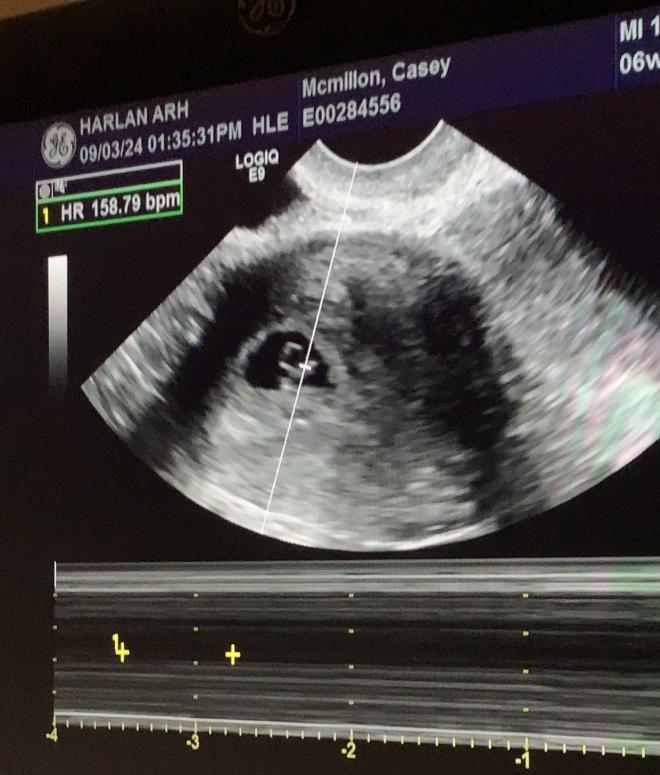

At the age of 37 I had been debating on having a hysterectomy August 21st 2024 I found out I was pregnant for the first time. I spent years trying I even took fertility medication and nothing. I have endometriosis and since I was 15 I have dealt with cysts. I was content with all my fur babies getting pregnant late in life wasn’t something I wanted to do and I had convinced myself I was okay with not having babies so once I was pregnant it was hard to get on board with at first. I went to the ER on September the 3rd 2024 to make sure I wasn’t having a epitopic pregnancy because I was scared to wait till my first appointment. The ultrasound picture is the ER visit there was a heartbeat 💓 and my numbers was growing everything was fine. That’s when I was coming around to having a baby finally! Then my first appointment September the 20th 2024 I found out there was no heartbeat. That destroyed me!! Here I was broken and trying to understand why this happened after all these years and dealing with the fact that I no longer will have my baby in my arms. Dr has no idea what happened we are left with the unknown and the heartbreak. Never got to know the gender. I had 4 names picked out for a boy same amount for a girl. My due date was April of 2025. Dr said I had a Missed Misscarriage because my body wasn’t recognizing the miscarriage. I carried till September the 25th 2024. I went into labor at home and went back a week later to make sure I passed everything on my own.

- Casey mcmillon bell